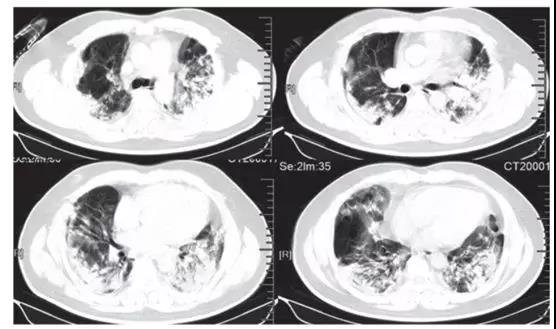

ICU患者入院時胸部CT圖像的典型發(fā)現(xiàn),是雙側(cè)多發(fā)小葉和亞段實變(見下圖)。